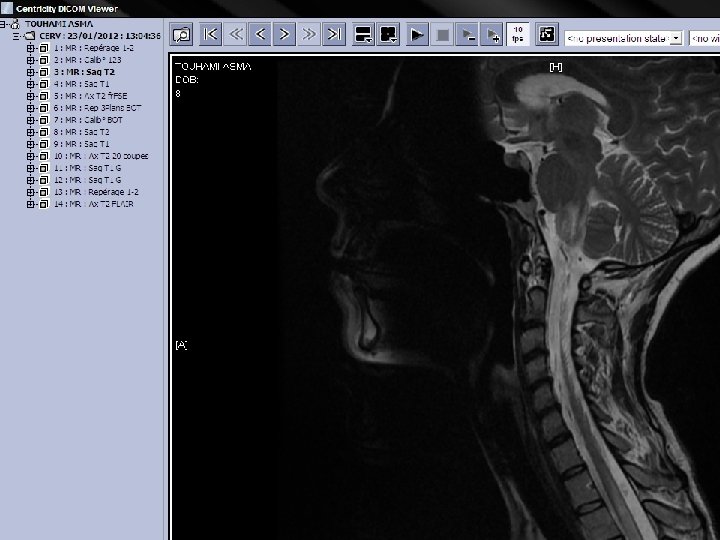

q IRM: d’hpersignaux sub blanche. Sur les séquences pondérées en T 2, les images ne sont pas spécifiques mais leur répartition et leur aspect évoquent des lésions de démyélinisation. Péri ventriculaire, en sub blanche profonde. Arrondies ou ovalaire, taille variable: qlq mm à qlq cm. Evocatrices en péri ventriculaire, sus tensorielle, médullaire.

Séquence T 1 après injection de Gadolinium st informative, les lésions rehaussées/Gado st évolutives. L’hyper signal induit /Gado est svt annulaire en périphérie de la lésion.

SEP Dissémination dans l’espace IRM: lésions multiples et sans R/ avec la symptomatologie apportée. La présence d’au moins 4 lésions dont 1 péri ventriculaire est significative. Dissémination dans le temps Aspect différent de lésions mais surtout le rehaussement de certaines d’entre elles témoignant de lésions d’ages différents.

Figure 1. IRM en séquence T 1 : « trous noirs » dans la substance blanche

Figure 2. IRM en séquence FLAIR : hypersignaux à prédominance périventriculaire.

Figure 3. IRM en séquence T 1 avec injection de gadolinium : lésions périventriculaires.

Figure 4. IRM en séquence T 2 : hypersignaux à prédominance périventriculaire.